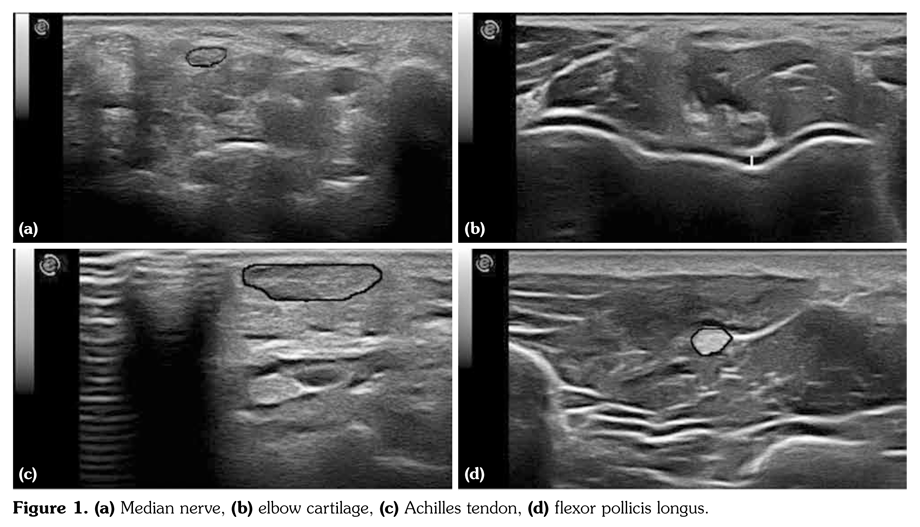

All subjects were examined with a commercial, real-time equipment (Esaote, Mylab 60, Genova, Italy) using a 6-18 MHz linear array transducer following a standardized scanning method. The same physician, experienced in musculoskeletal US, who was blinded to patients’ data performed all the ultrasonographic measurements involving distal humeral cartilage thickness, cross sectional area (CSA) for flexor pollicis longus (thenar region), Achilles tendon (at the level of the medial malleolus), and median nerve (at carpal tunnel entrance) (Figures 1a-d). To increase the accuracy of measurements, all images were also evaluated by another researcher experienced in US for more than 5 years.